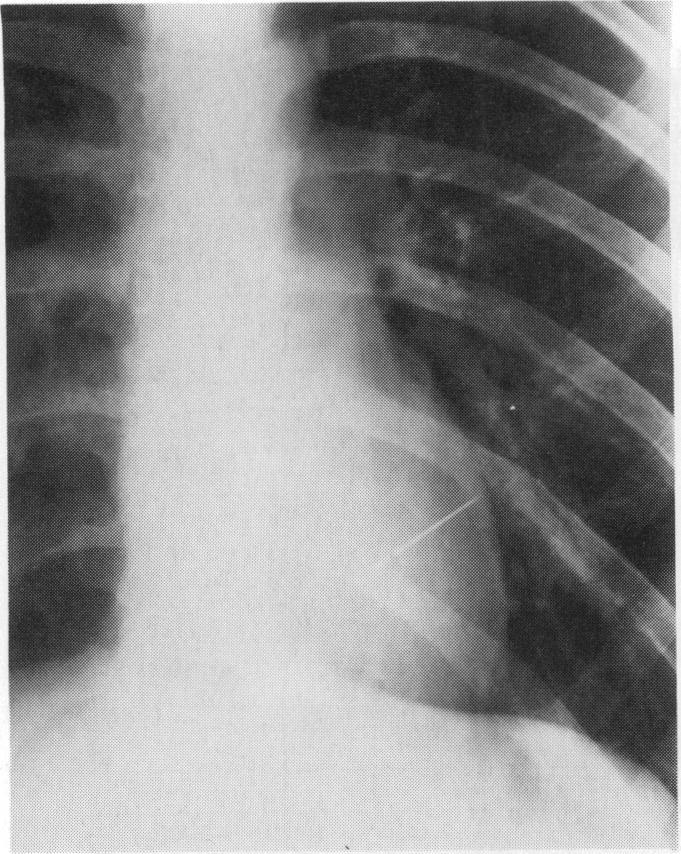

Needle injury to the heart.

Arch Emerg Med. 1992 Mar;9(1):54-7. doi: 10.1136/emj.9.1.54.

https://cdn.ncbi.nlm.nih.gov/pmc/blobs/5516/1285828/f09bfe5d5ff9/archemed00033-0075-a.jpg

https://cdn.ncbi.nlm.nih.gov/pmc/blobs/5516/1285828/a8141ba0acff/archemed00033-0074-a.jpg

https://cdn.ncbi.nlm.nih.gov/pmc/blobs/5516/1285828/1626a11aa9cf/archemed00033-0074-b.jpg